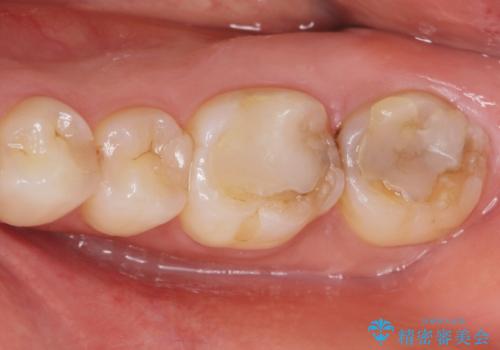

奥歯のザラザラが気になる

- 奥歯のザラザラが気になり、白い被せ物をしたいとのことで来院。

レントゲンや拡大鏡で確認をしたところ歯の表面は粗造になっていたが

う蝕があるわけではないので以下の提案を行った。

歯の表面が粗造なのは虫歯ではないが

歯の表面が溶けはじめて、虫歯になりやすい状態になっています。

表面がツルツルした白い被せ物が入り、大変満足して頂けました。